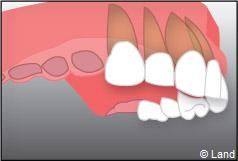

Exemple d’un implant unitaire pour remplacer une dent antérieure manquante.

Les implants peuvent aussi servir à stabiliser un appareil amovible au maxillaire supérieur comme au maxillaire inférieur. Dans ce cas, les implants retiennent la prothèse amovible par des systèmes d’attachement.